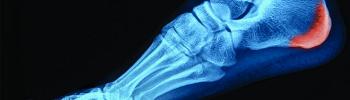

Espolón Calcaneo y Fascitis Plantar - FisioClinics

Tratamiento de Espolón Calcaneo y Fascitis Plantar